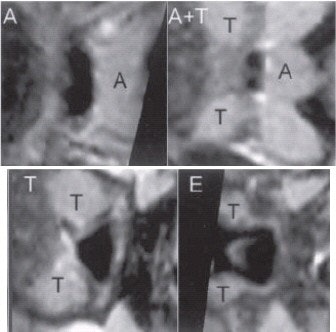

| A gray-level, 2-D scene of the cross section of the airway orthogonal to the centerline at marked locations A (adenoid), A and T (adenoid and tonsil overlap), T (tonsils), and E (epiglottis). |